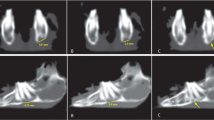

In both study groups, the micro-CT radiological analysis indicated higher radiological bone union scores for BCs + BFPSCs filling than BCs alone with a statistically significant difference at both 4 weeks (group 1 p = 0.015 and group 2 p = 0.022) and 8 weeks after surgery (group 1 p = 0.008 and group 2 p = 0.018) (Table 1, Fig. 4). BMD was higher in both study groups when bone defects were filled with BCs + BFPSCs than when BCs were used alone, with statistically significant differences at both 4 weeks (group 1 p = 0.021 and group 2 p = 0.021) and 8 weeks after surgery (group 1 p = 0.020 and group 2 p = 0.021) (Table 2).

Micro CT analysis (radiological bone union). A Score 0 (no noticeable new bone formation), mandible at 4 weeks post-surgery of an osteoporotic rat treated with BC alone. B Score 1 (cortical bone thickening along the margins of the mandibular symphysis), mandible at 4 weeks after surgery of a healthy rat treated with BC alone. C Score 2 (bone union with apparent cracks/fissures), mandible at 8 weeks after surgery of an osteoporotic rat treated with BC + BFPSCs. D Score 3 (bone union with or without trace of cracks/fissures), mandible at 8 weeks after surgery of a healthy rat treated with BC + BFPSCs